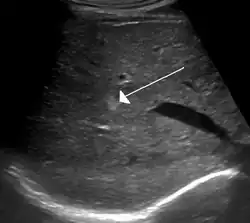

Hemangioma no fígado visto em ultrassom.